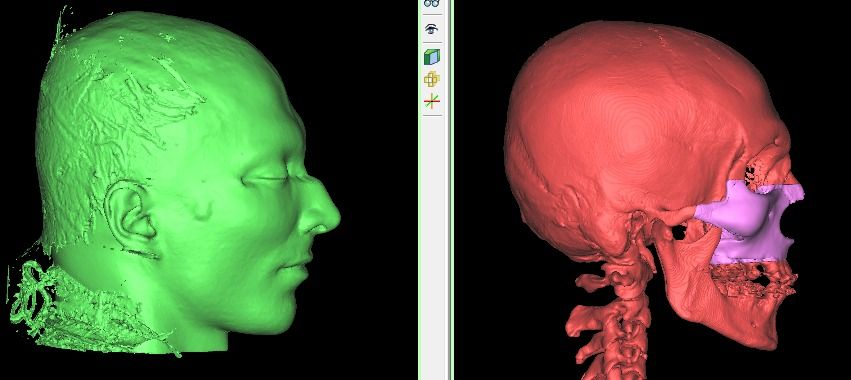

I know a guy who designed this for himself in collaboration with an asian implant company.

Not the final product yet, he is making adjustments as we speak.

Giant and Eppley were the inspiration